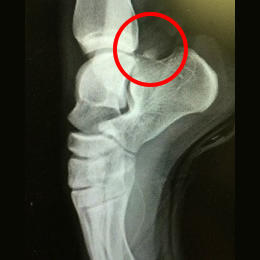

バレエダンサーや、サッカー選手は足関節を底屈(足首を伸ばす)することが多く、足首の後ろ側を痛める事が多く見られます。

足関節の距骨という骨の後ろ側が大きく突き出していたり、離れて過剰骨となっている人(三角骨といいます)が何度も足関節を底屈すると、その骨が脛骨と踵骨の間に挟まりこみ(インピンジメント)足関節の後方に炎症を起こし、痛みの原因となるのです。

![]() 三角骨(距骨の後ろ側の骨) |

![]() 足首を伸ばす(底屈する)ことで挟まりこむ |